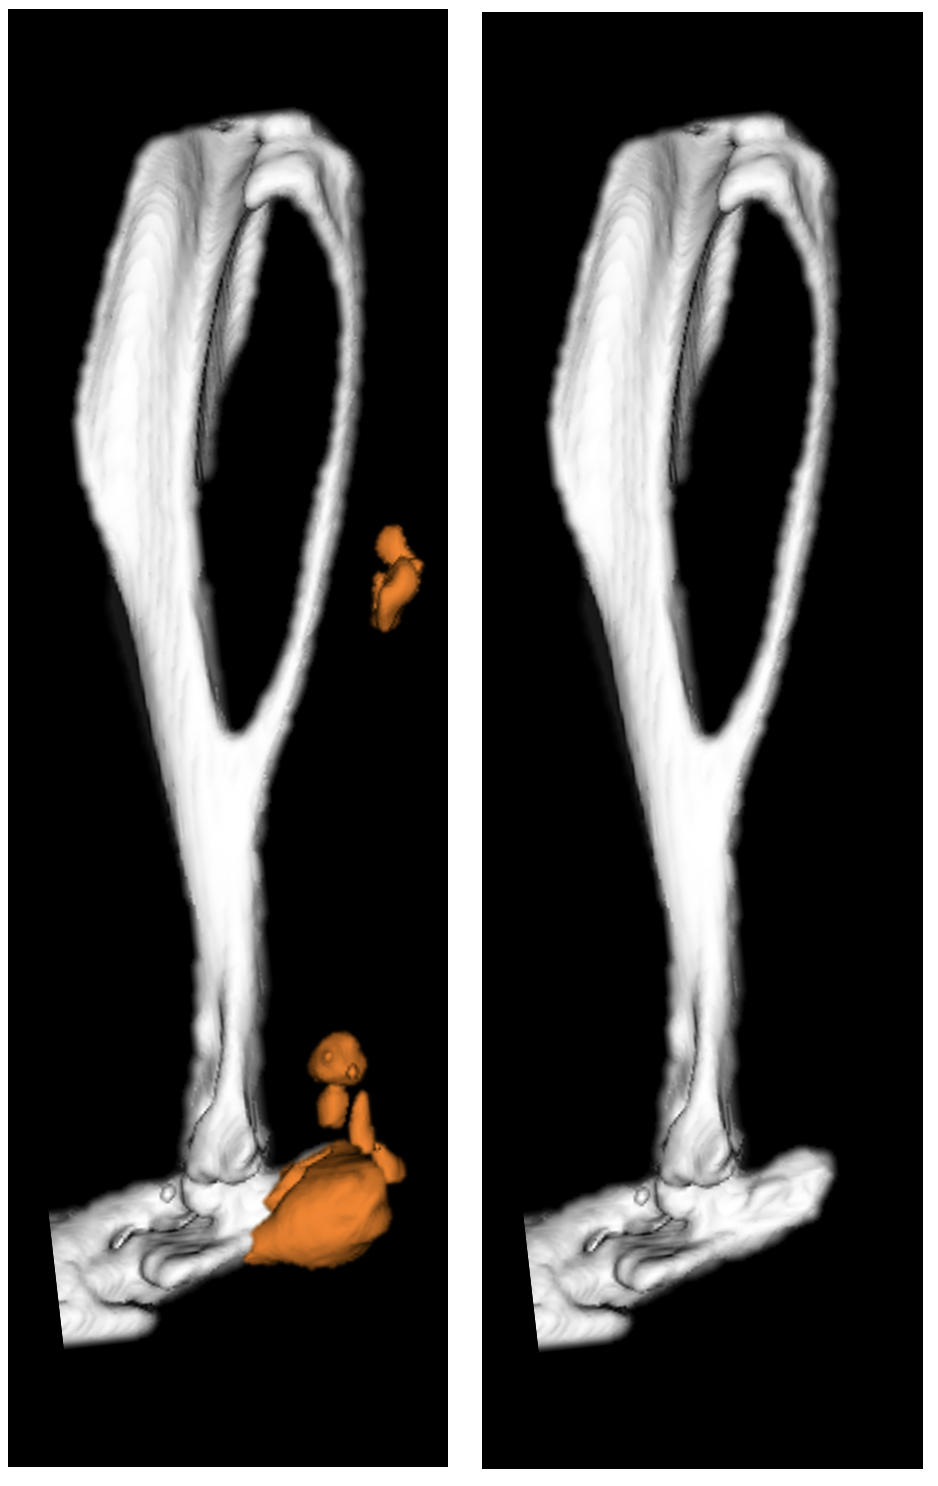

Mouse hindlimb uCT: Levi Lab has generated a mouse model that reliably and reproducibly replicates the formation of human traumatic heterotopic ossification allowing for in vivo studies of the debilitating disease